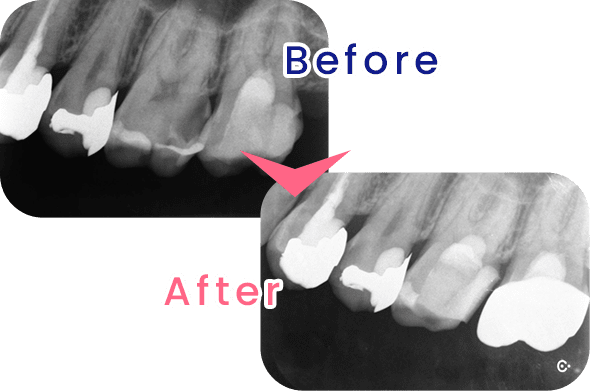

虫歯が歯髄(歯の神経)に達すると、歯髄を取る(抜髄)という処理が必要になりますが、こうした歯を残すことのできる、MTAセメントを使用した断髄という治療法が注目されています。断髄とは虫歯が進行したところまでの組織を取り除き、MTAセメントで蓋をすることにより、神経の生活反応を残したまま保存する方法です。

当院の虫歯治療

米国の歯内療法専門医が行う術式による治療です。先端設備と高度な治療を用いることで、従来の根幹治療では治療が難しかった症例でも、歯を残すことのできる確率を高めることが可能になります。